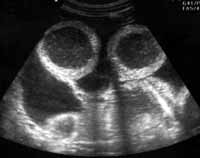

Рис. 1. Эхограмма больного с механической тонкокишечной непроходимостью - спаечный процесс на уровне проксимальных отделов подвздошной кишки. При продольном сканировании на уровне тощей кишки отмечается внутрипросветное депонирование жидкости, расширение просвета тонкой кишки, утолщение складок.

[Увеличить]

Рис. 2. Тот же больной. Поперечное сканирование.